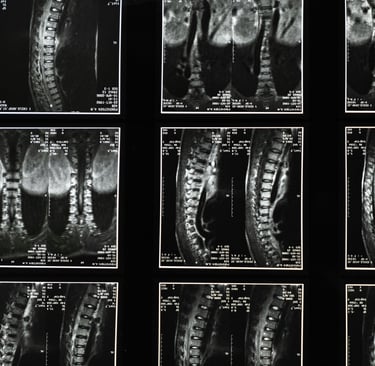

Degenerative Disc Disease is a term used to describe wear-and-tear changes in the spinal discs—the cushions between the bones of your spine. These discs naturally lose hydration and flexibility over time.

Many Brookfield residents are surprised to learn that disc degeneration often shows up on imaging even when there is little or no pain.

Importantly, imaging results do not always correlate with pain levels. Treatment should focus on how you feel and function—not just what an MRI says.